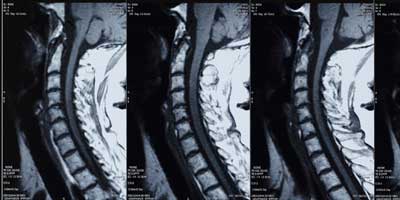

多年来,弗雷博士一直站在新的非手术治疗betway体育亚洲登录脊柱外科技术. 该研究所一直致力于将先进的微创外科技术引入科罗拉多州。CCSI在使用脊髓刺激器用于高级疼痛管理。George Frey博士是一位著名的创新者,他因开发椎弓根螺钉导航和3D成像及打印的新技术而广受认可。